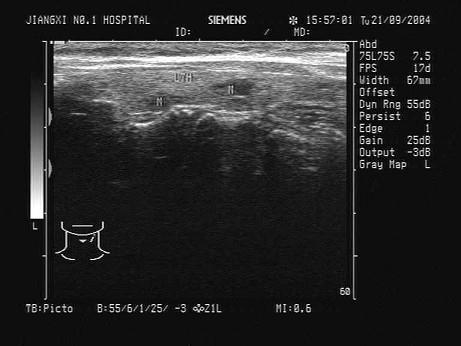

问题 患者感颈部肿胀1年余。根据超声声像图,诊断为?(?)

选项 A.多发腺瘤 B.结节性甲状腺肿并囊变 C.甲状腺囊肿 D.甲状腺癌 E.甲状腺炎

答案 B